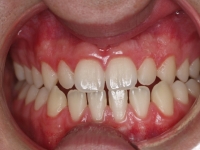

El paciente E.A. acude a nuestra consulta por diastema inferior y ausencia de contactos en los sectores laterales.

Chica de 17 años tratada en 1 año con stripping en los dientes inferiores